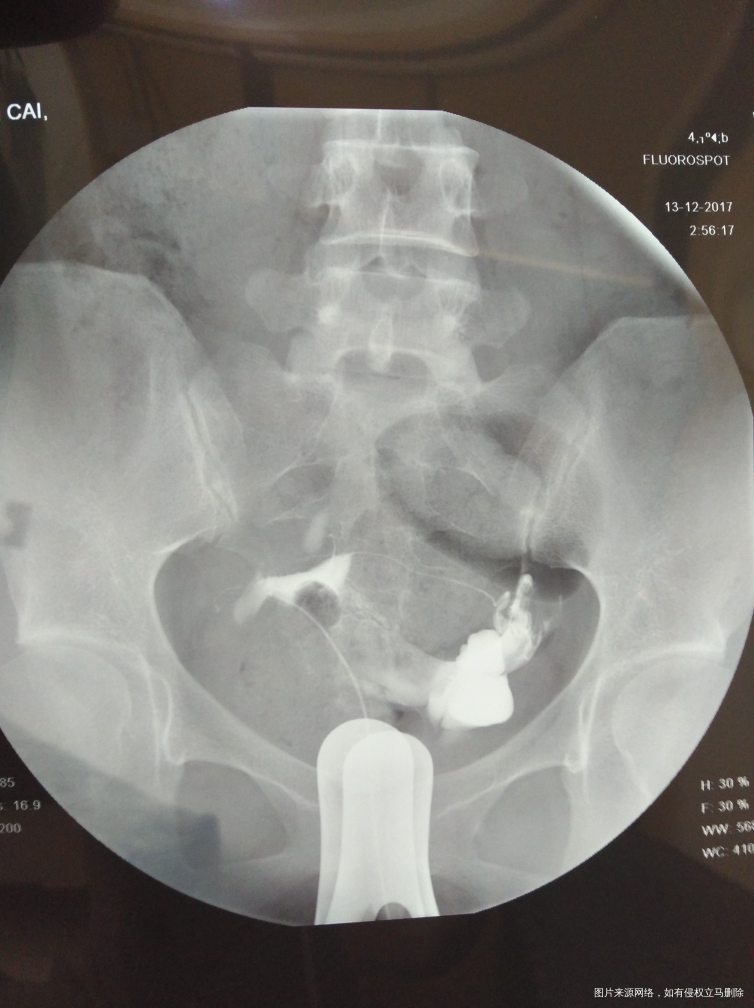

麻烦医生指点,输卵管通而不畅要怎么治疗?我的右侧输卵管部分切除,所有希望都寄托在这跟管上了,我不想试管,想自然怀孕,帮帮忙指点

,谢谢!从哪里看的出通而不畅的,也帮忙指点一下

您好,你这种情况考虑试管婴儿比较合适您,从图上看还有盆腔炎,如果你不想试管坚持自己试可以考虑手术,术后自然妊娠几率低,请慎重考虑

你好,从您的片子看,盆腔弥散局限,所以输卵管通而不畅。可以选择中药治疗。最多半年,如果不怀,可以选择手术或者试管。祝您早日好孕。如果满意我的回复,记得采纳。

你好,从您的片子看,盆腔弥散局限,所以输卵管通而不畅。可以选择中药治疗。最多半年,如果不怀,可以选择手术或者试管。祝您早日好孕。